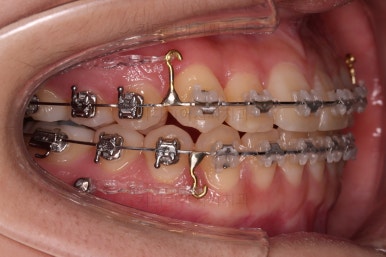

이제부터는 미니스크류를 이용해서 치열을 뒤로 잡아당겨 주면서 뻗침이나 벌어져 보이는 형태를 개선해 줍니다.

점점 느낌이 좋아지는 걸 볼 수 있죠?

중간중간 얼구랏지능ㄹ 보며 함께 치료 목표에 대한 대화를 나누게 됩니다.

입매 괜찮은지, 배열된 느낌, 뻗친 느낌 등등

개선하고 싶은 부분, 개선하려면 추가로 필요한 기간이나 장치 등을 말씀 나누면서 결과를 타협해 나갑니다.

모든 사람 몸ㅁ은 100점은 있을 수 없기 때문에 그리고 1~2점 점수 높이려고 시간을 무한정 쓸 수는 없기 때문에 협의해 나가는 과정이 중요하죠.

이번 환자분은 약간의 뻗친 느낌이 없지 않았지만 현재로도 맍고하셨고 얼른 끝내고 싶어하셔서 필수적으로 해야 되는 부분만 추가로 마무리 과정에서 잡아주고 치료를 종료하게 됩니다.